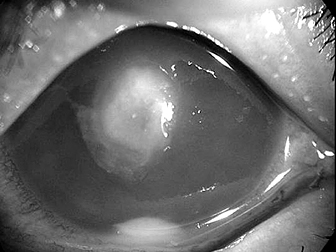

数あるコンタクトレンズ合併症の中で、最も病状が重くなるのはアカントアメーバ感染症です。水道水などを介して侵入し、ケース内で増殖したアカントアメーバがコンタクトレンズを介して角膜に感染を起こしますが、ルーズな装用(時々使用する、あまりレンズケアをしない、指定期間を越えて使用する、水道水で洗浄)をしている人に圧倒的に多く見られます。

抗真菌薬の投与や病変の

アカントアメーバによる角膜感染